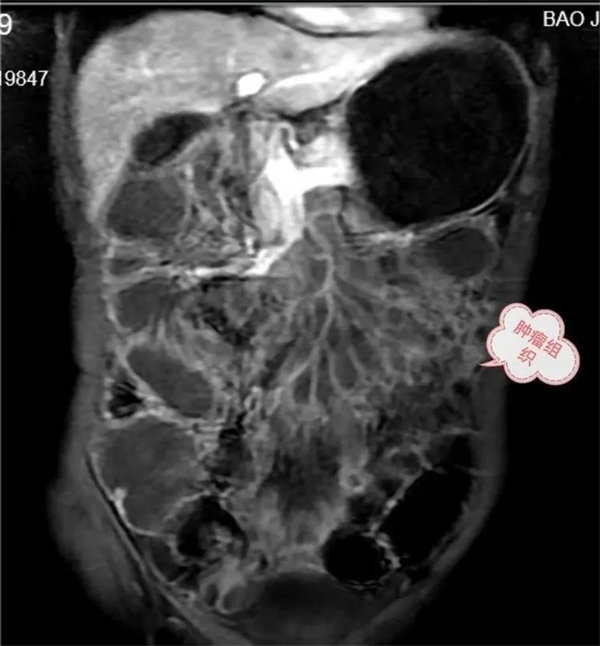

病例1:患者,老年男性,以腹痛腹脹不適就診,常規腹部CT,腸系膜血管CT成像,由于腸管堆積,內容物影響,病變與腸管密度差別不大,未發現明顯病變。經多學科會診商討后,建議行小腸磁共振成像(MRE)檢查,進一步查明病因。

圖1,胃,小腸,結腸充盈顯示良好,局部小腸壁增厚,腸系膜病變組織包繞腸系膜動脈及分支血管塑形生長呈等T1,等T2信號腫塊。

圖2,動脈期,病灶無明顯強化,邊緣輕度強化。

圖3:延遲期,顯示腸系膜根部病變逐漸輕度強化。胃,結腸充盈顯示良好,腸壁強化,未見異常。